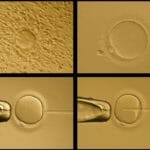

Intracytoplasmic Sperm Injection (ICSI)